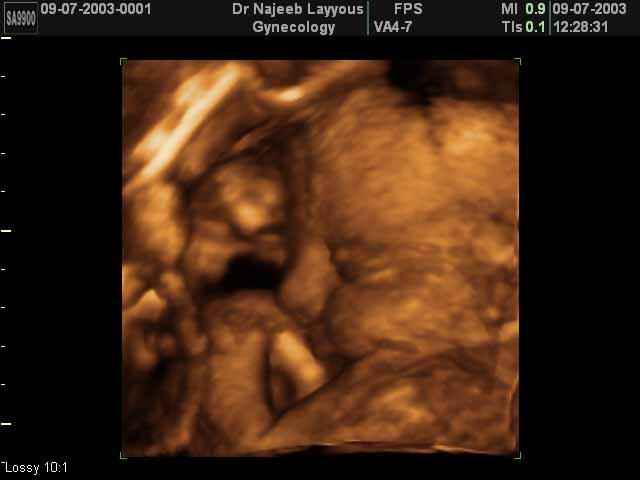

صور جانبية لرأس الجنين بجهاز الالتراساوند ثلاثي الأبعاد | الدكتور نجيب ليوس